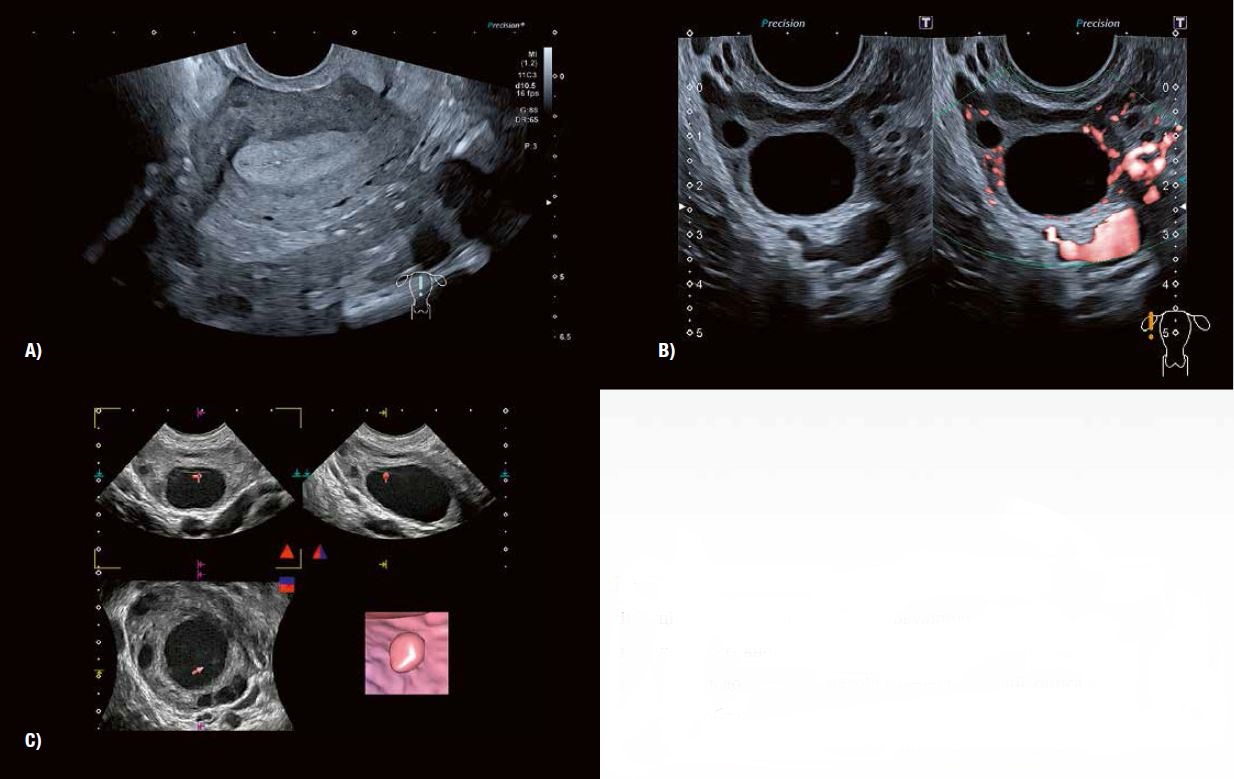

Рис. 1: Детальне зображення морфології яєчників  за допомогою 3D-реконструкції в сірій шкалі та візуалізації Shadow Glass відповідно. Розширена 3D-візуалізація візуалізує стійку, заповнену згустками лютеїнову кісту,  незрілі фолікули перед овуляцією, антральні фолікули,  а також атретичні фолікули та залишки фолікула, що пройшов овуляцію.

Протягом усього циклу між початком менструації та менопаузою кора яєчників підтримує фолікули на різних стадіях розвитку. Ті, що видно на ультразвуковому дослідженні, варіюються від багатьох антральних фолікулів до ряду незрілих фолікулів і, як правило, одного домінантного передовуляційного (граафського) фолікула (рис. 1 + 3).

Рис. 3 A: 3D анатомічні площини показують типову мультифолікулярну природу структури фолікулів яєчників у віковій групі від раннього до середнього та пізнього підліткового віку.

Рис. 3 B демонструє зміну характеристик фолікулів та строми у жінок, наприклад, у віці від 25 до 39 років, особливо після пологів.

Рис. 3 C: Типовий вигляд у віковій групі 40 років.

Рис. 3 D: 2D- та 3D-зображення (Luminance) показують фолікули жінок у віці від 45 до 50 років. На відтвореному зображенні чітко видно контури фолікулів, що складаються з гранульозних та текальних клітинних шарів.

Ультразвукове дослідження та моніторинг росту фолікулів під час природного або пов'язаного з допоміжними репродуктивними технологіями циклу вже давно стали загальноприйнятою практикою. Прогрес у технології УЗД значно підвищив можливості оцінки дозрівання фолікулів та прогнозування початку овуляції (рис. 5). Сканування у високій роздільній здатності в сірій шкалі демонструє потовщення стінки фолікула внаслідок розвитку гранульозних та текальних клітин. Внутрішнє відшарування гранульозних клітин можна виявити в овуляційному фолікулі. 3D-візуалізація Fly Thru часто дозволяє розпізнати кумулюсну масу безпосередньо перед овуляцією (рис. 6). Розмір фолікула на початку овуляції може варіюватися від 1,8 до 3,0 см. Примітка: розмір фолікула сам по собі не завжди є показником його дозрівання.

SMI показує збільшення периферичної васкуляризації, пов'язаної з дозріванням фолікулів (Граафа). Він також дозволяє точно виміряти час овуляції в рамках циклу, що контролюється. Було доведено, що підвищена васкуляризація пов'язана  з овуляційним статусом і розвитком сприятливого ендометрію в періоді овуляції (рис. 5 + 6). Дослідження показали хорошу кореляцію між периферичним ангіогенезом фолікула в періоді овуляції та після овуляції з рівнями естрогену та прогестерону в сироватці крові відповідно. SMI забезпечує  надійний засіб оцінки функції лютеїнової фази як частини моніторингу фертильності та оцінки дуже  ранньої вагітності (рис. 9+13).